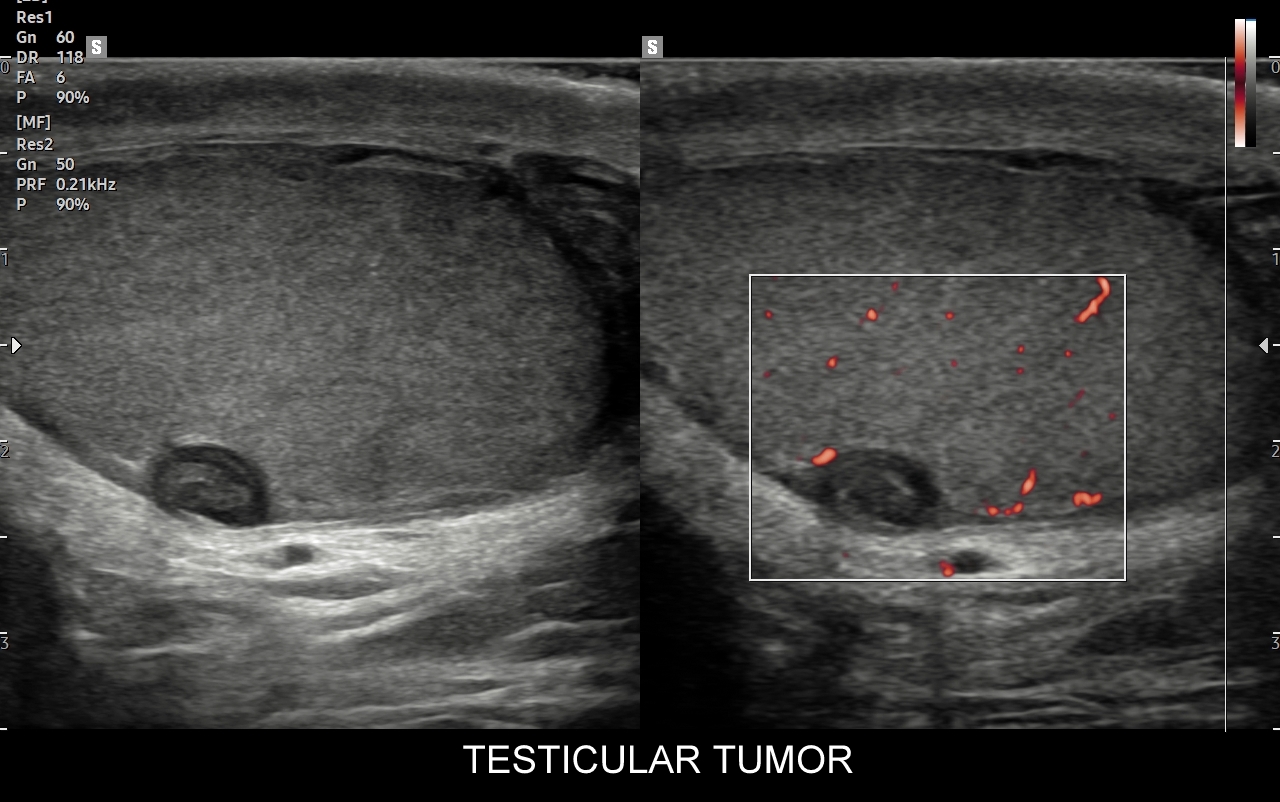

Mosznę bada się aparatem USG wyposażonym w dedykowaną sondę o wysokiej rozdzielczości przeznaczoną do oceny jąder i drobnych struktur moszny, koniecznie z zastosowaniem trybów dopplerowskich, takich jak Doppler kodowany kolorem, Doppler spektralny i obrazowanie mikrounaczynienia. Dopełnieniem badania USG jąder jest użycie w stosownych przypadkach trybu elastografii oraz trybu USG z kontrastem (CEUS). Lekarzem, który pierwszy we Wrocławiu i na Dolnym Śląsku przeprowadził badanie CEUS jąder jest dr Tomasz Szczepański.